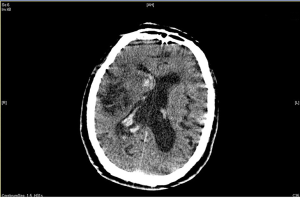

Atrial fibrillation is an important risk factor for ischemic stroke, and about 25% of ischemic stroke patients have atrial fibrillation (12). Lee et al.’s study showed that previous history of atrial fibrillation was an independent risk factor for intracranial hemorrhage after intravenous thrombolysis. Patients with ischemic stroke accompanied by atrial fibrillation were often treated with anticoagulant therapy, and the incidence of intracranial hemorrhage was significantly increased (13-15). In this study, the results of logistic regression analysis showed that atrial fibrillation was an independent risk factor for hemorrhage after thrombolysis, which was consistent with literature reports (16,17). It is suggested that for ischemic stroke patients with atrial fibrillation, clinical nurses should closely monitor the occurrence of hemorrhage during thrombolysis and within 24 hours after thrombolysis. Immediate brain CT/MRI examination should be conducted when the amount of peripheral hemorrhage increases, and when continuous hemorrhage or the neurological symptoms deteriorate, so as to evaluate the extent of disease changes in a timely manner, as shown in Figures 2 and 3.

Hemorrhage at different sites within 24 hours of thrombolysis was counted, including intracranial hemorrhage (symptomatic and non-symptomatic hemorrhage) (7,8) and peripheral hemorrhage (hemorrhage of the gums, oral mucosa, skin and mucosa, nose, digestive system, and urinary system). The diagnosis of intracranial hemorrhage during intravenous thrombolysis or within 24 hours after thrombolysis was based on head CT/MRI examination when the patient’s clinical symptoms were aggravated (9). In this study, all hemorrhage after thrombolysis was spontaneous.